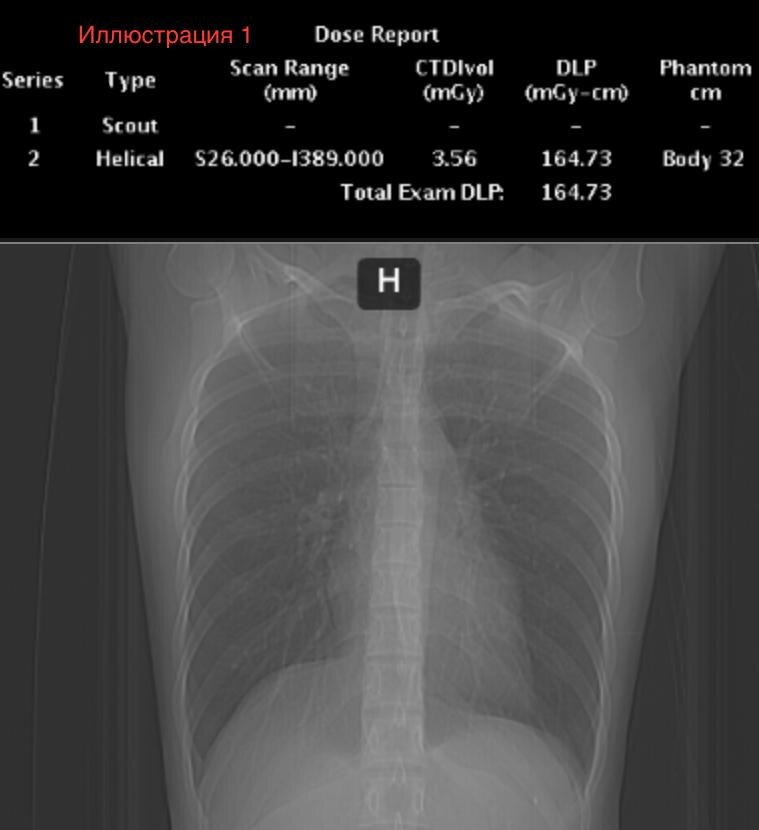

1. Сверху будет Dose Report . У этих DR есть одно новое поле «Scan range» - это протяженность сканирования. Самое главное, на что мы должны обратить внимание - это DLP. Но обращайте внимание и на протяженность сканирования - это важно! Как определить протяженность сканирования - я укажу ее в каждом кейсе, а как её определить исходя из DR - это будет задание для вас!

2. Снизу будет фронтальная топограмма - глядя на нее, вы можете примерно оценить комплекцию пациента.

Исследования выполнены в одном и том же ЛПУ на одном и том же аппарате и на одинаковых протоколах сканирования.

Ваша задача: оценить, насколько сильно меняется DLP у разных пациентов и сделать предположения , почему DLP меняется.

Иллюстрация 1. КТ ОГК. Длина сканирования 415 мм. DLP 164,73. Эффективная доза 2,8 мЗв.

Вывод №1. На иллюстрации 1 довольно худой пациент, а у пациента на иллюстрации 2 подкожная клетчатка выражена избыточно, что видно по топограммам. По цифрам мы видим, что DLP у худого и полного пациентов могут отличаться в три раза! Это значит, что масса тела имеет прямое влияние на дозу. В моей практике я встречал пятикратную разницу, если сравнивать истощенных пациентов с кахексией и пациентов с ожирением четвертой степени!